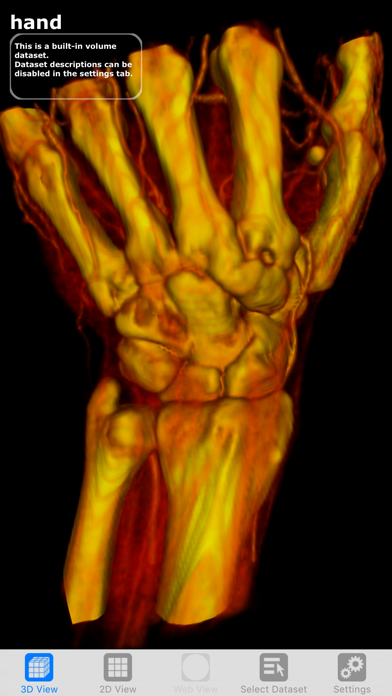

Скриншоты

Visualizing the Future of Biomedicine